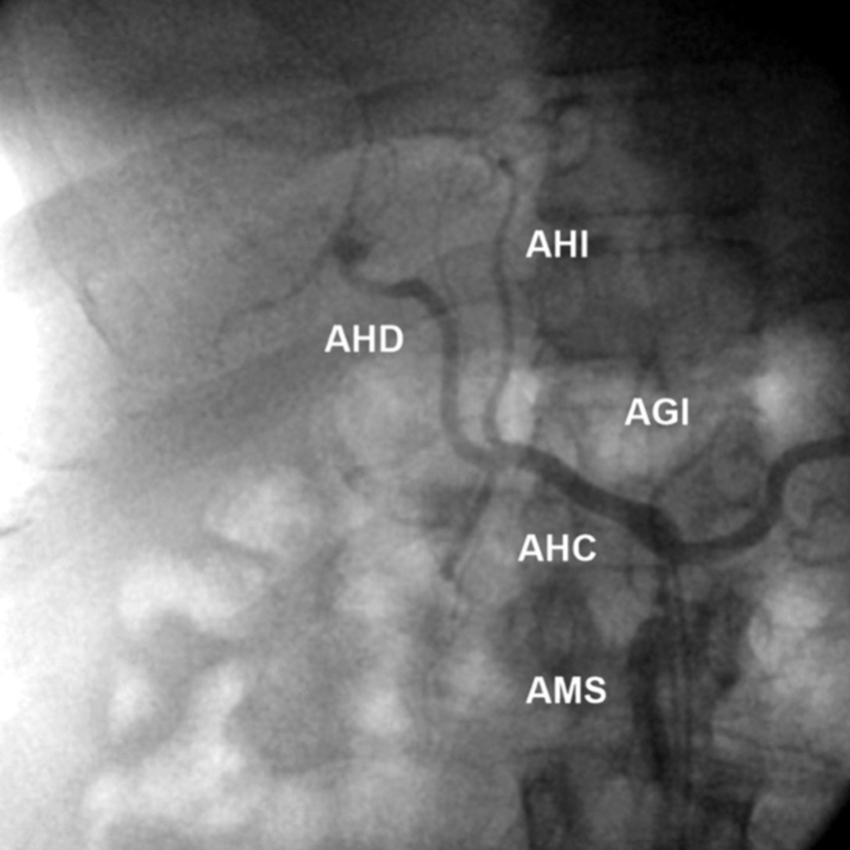

Tipo 3: AHD aberrante con origen en la AMS. AHI con origen en la AHC (Figs. 6 y 7).

La población estudiada fue de 275 pacientes, con una edad mediana de 58.5 años y de sexo masculino el 73.1% (n = 201). Se han constatado las variantes tipo 1 (normal) de anatomía de la arteria hepática en 192 casos (69.8%), tipo 2 en 18 casos (6.5%), tipo 3 en 19 casos (6.9%), tipo 4 en 7 casos (2.5%), tipo 5 en 4 casos (1.5%), tipo 6 en 3 casos (1.1%), tipo 7 en 2 casos (0.7%), tipo 8 en 7 casos (2.5%), tipo 9 en 17 casos (6.2%).

La variante anatómica más frecuente de vascularización hepática en esta investigación fue el tipo 1, que hemos encontrado en un 69.8% de nuestra serie. Esta frecuencia es superior a la descrita por Michels5) (55.0%) y Covey et al. (16) (61.3%); no obstante, es inferior a la reportada en la serie de Song et al. (17) (89.1%) y la revisión de Noussios et al. (15) (81.0%) (Tabla 1).

Las siguientes variantes más frecuentes halladas fueron los tipos 2, 3 y 9. Las prevalencias de los tipos 2 y 3 fueron cercanas a la reportada por Fonseca-Neto et al. (18; asimismo, destacamos la prevalencia aumentada de la variante de Michels tipo 9 en nuestra serie comparada con otras publicaciones5,13,15,17,19. Al igual que Covey et al. (16, no hemos detectado la variante de Michels tipo 10; sin embargo, observamos otros hallazgos infrecuentes fuera de la clasificación de Michels, como dos casos de tronco celíaco-mesentérico (0.7%), ausencia del tronco celíaco (emergencia independiente de la AHC y esplénica), AHI accesoria emergente de la AGD y la emergencia de las AHD e AHI aberrantes de la AMS. También hallamos tres casos con arco de Bühler (1.1%), con una frecuencia similar a la de otros reportes (1.0 a 4.0%)20.